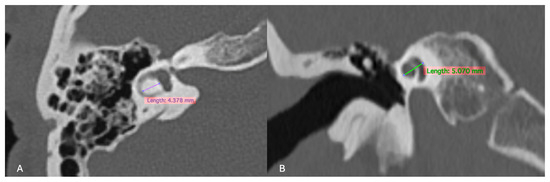

For the inner ear structures, we assessed the density of the otic capsule, the spiral structure, and the internal relationships, including the densities of the cochlea, vestibule, and semicircular canals. Cochlear malformations were classified according to the classification initially proposed by Jackler et al. [5] and later refined by Sennaroğlu and Saatçi [6]. Additionally, measurements of the cochlear height in the coronal section and the diameter of the bony island of the lateral semicircular canal (LSCC) in the axial section, as described by Purcell et al. [13], were taken for all patients to explore differences between congenital and acquired cases (Figure 2). Axial sections were aligned parallel to the LSCC, and coronal sections were defined as perpendicular to the axial sections. The VA was examined, and cases where the diameter exceeded 1.5 mm at its midpoint were identified as having a large VA.

Figure 2.

(A) Measurement of the LSCC (left semicircular canal) bony island in the axial section and (B) measurement of the height of the cochlea in the coronal reformatted section as described by Purcell et al. [13].

Measurements of cochlear height and the width of the LSCC bone island, as defined by Purcell et al. [13] in all patients. The patients were categorized into three groups: those with cochleovestibular anomalies (56 ears), patients with congenital SNHL but without detectable anomalies on imaging (298 ears), and those with acquired SNHL (214 ears). In the anomaly group, cochlear morphology in 4 ears was too distorted to measure the height, leaving 52 ears for evaluation. These ears showed significantly reduced cochlear height compared to the 512 ears without anomalies (p < 0.001). Additionally, the 298 ears with congenital hearing loss but without detectable anomalies had a lower mean cochlear height than the 214 ears with acquired hearing loss (p < 0.001). Of the 56 ears with congenital anomalies, 27 lacked detectable LSCC, leaving 28 ears available for evaluation. In the acquired SNHL group, LSCC assessability was compromised in 3 ears due to otosclerosis and trauma, allowing for the assessment of 211 ears. Notably, the LSCC bone island width was significantly lower in the anomaly group (28 ears) compared to the combined non-anomaly groups (509 ears) (p = 0.012). However, there was no significant difference in LSCC island width between the congenital SNHL group without anomalies and the acquired SNHL group. These findings suggest that cochlear height might be a more reliable indicator than LSCC bone island diameter for identifying congenital SNHL.

In 2006, Purcell et al. [13] suggested that measurements of cochlear height and LSCC bone island width could serve as indicators of congenital malformations even in ears that appear morphologically normal. According to the data we obtained from this study, the following can be said:

- Cochlear height was significantly lower in patients with anomalies compared to those without, and it was also lower in patients with congenital hearing loss without anomalies compared to those with acquired hearing loss;

- LSCC bone island width was notably reduced in patients with anomalies compared to those without. However, for congenital SNHL patients without anomalies, the LSCC island width did not show a significant difference when compared to acquired SNHL patients;

- These findings suggest that cochlear height might be a more reliable predictor than LSCC bone island diameter for identifying congenital SNHL.